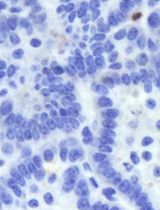

To take a snapshot: highlight one of the control wells and a single field of view. Then, within the Channel Selection window, click Snapshot in any of the channels to take one image to check if the leukemia cells are in focus. If cells are not in focus, change the heights for CyQuant Green and Brightfield channels until the cells are in focus (Figure 2).

Figure 2. Fluorescence imaging using a 20× objective of a primary patient leukemia sample overlaid with mesenchymal stromal cells (MSCs) stained with CyQUANT Green. White arrows indicate MSCs, and red arrows indicate leukemia cells.